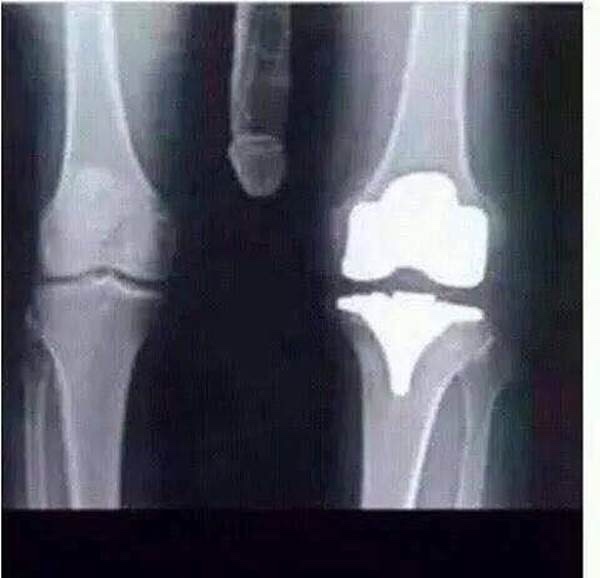

Messed my knee up the other day. Doc says it's real bad. I took a pic of the X-ray

http://hotrodforums.net/forums/image...2014/12/25.jpg